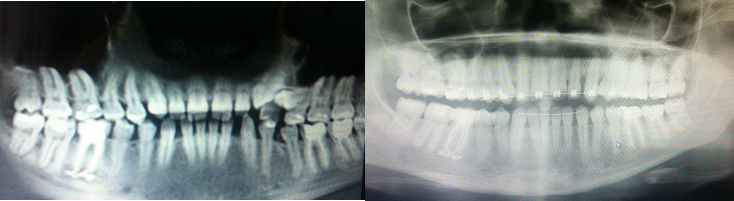

Фотографии и схемы для ОПТГ и мезиального прикуса